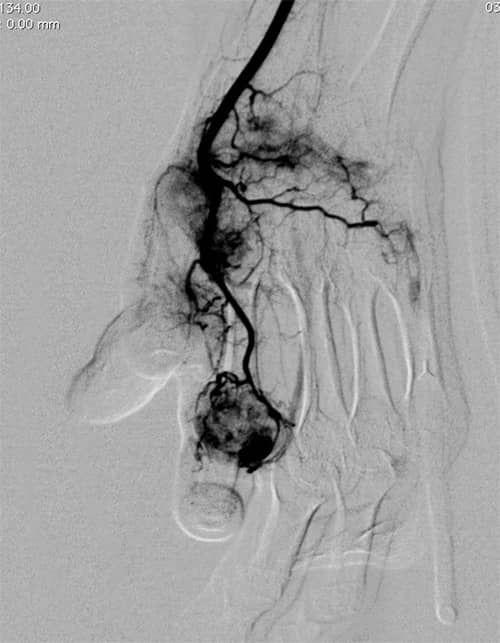

正常な血管と異常な血管とは?